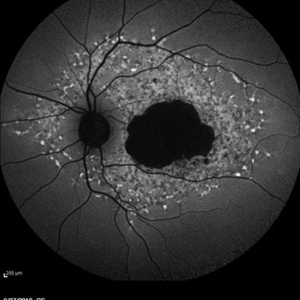

Late Stage Stargardt's Disease Late Stage Stargardt's DiseaseMar 13 2013 by Hamid Ahmadieh, MD Autofluorescence imaging of the right eye of a 46-year-old man with decreased VA due to advanced Stargardt's disease. Photographer: Nayereh Hadipoor, Negah Eye Center, Tehran Imaging device: Heidelberg Spectralis Condition/keywords: autofluorescence imaging, Stargardt disease

Late Stage Stargardt's Disease Late Stage Stargardt's DiseaseMar 13 2013 by Hamid Ahmadieh, MD Autofluorescence imaging of the left eye of a 46-year-old man with decreased VA due to advanced Stargardt's disease. Photographer: Nayereh Hadipoor, Negah Eye Center, Tehran Imaging device: Heidelberg Spectralis Condition/keywords: autofluorescence imaging, Stargardt disease